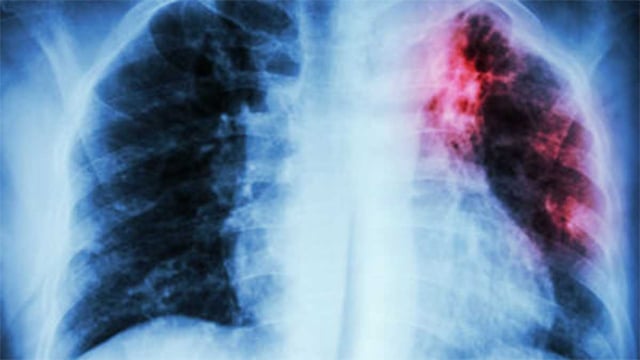

New Hampshire Identifies Two Active TB Cases With Public Exposure in Manchester and Nashua

• DHHS says two people with active tuberculosis were infectious while in Manchester and Nashua, prompting targeted outreach.